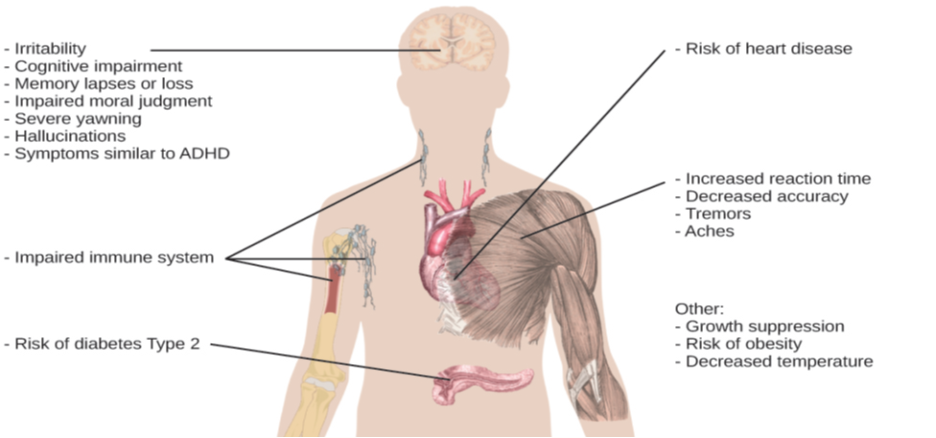

When people have difficulty getting sleep due to their work or the demands of day-to-day life, they accumulate a sleep debt. A person with a sleep debt does not get sufficient sleep on a chronic basis. The consequences of sleep debt include decreased levels of alertness and mental efficiency. Interestingly, since the advent of electric light, the amount of sleep that people get has declined. While we certainly welcome the convenience of having the darkness lit up, we also suffer the consequences of reduced amounts of sleep because we are more active during the nighttime hours than our ancestors were. As a result, many of us sleep less than 7–8 hours a night and accrue a sleep debt. While there is tremendous variation in any given individual’s sleep needs, the National Sleep Foundation (n.d.) cites research to estimate that newborns require the most sleep (between 12 and 18 hours a night) and that this amount declines to just 7–9 hours by the time we are adults.

Given the central role that sleep plays in our lives and the number of adverse consequences that have been associated with sleep deprivation, one would think that we would have a clear understanding of why it is that we sleep. Unfortunately, this is not the case; however, several hypotheses have been proposed to explain the function of sleep.

Cognitive Function of Sleep

Another theory regarding why we sleep involves sleep’s importance for cognitive function and memory formation (Rattenborg, Lesku, Martinez-Gonzalez, & Lima, 2007). Indeed, we know sleep deprivation results in disruptions in cognition and memory deficits (Brown, 2012), leading to impairments in our abilities to maintain attention, make decisions, and recall long-term memories. Moreover, these impairments become more severe as the amount of sleep deprivation increases (Alhola & Polo-Kantola, 2007). Furthermore, slow-wave sleep after learning a new task can improve resultant performance on that task (Huber, Ghilardi, Massimini, & Tononi, 2004) and seems essential for effective memory formation (Stickgold, 2005). Understanding the impact of sleep on cognitive function should help you understand that cramming all night for a test may be not effective and can even prove counterproductive.